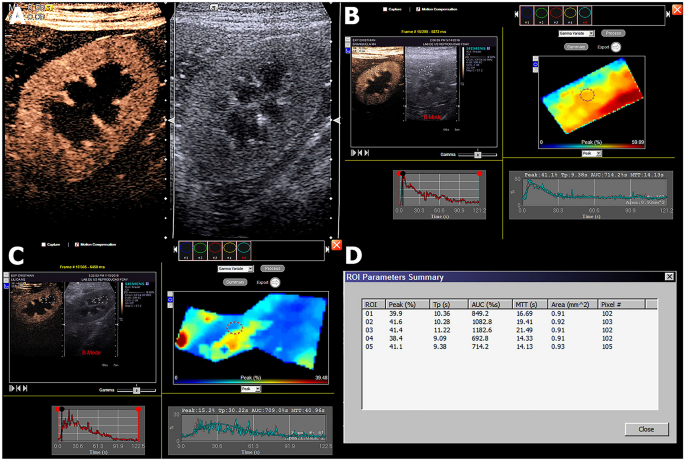

After acquisition, the images were transferred to an off-line analysis module (DICOM, Digital Imaging and Communications in Medicine, National Electrical Manufacturers Association). Two trained evaluators, blinded to the treatment, analysed each of the image sequences obtained. The main areas of interest were defined in the renal cortex (Cort) and then medulla (Med). After automatic assembly of the image sequence, these were converted into time-intensity curves (TIC). Five subareas of interest (ROI) were drawn, each approximately 1 mm2. These ROI were located within the cortical or medullary parenchyma and were uniform in depth, as described by Wei et al.32. Based on the TIC, the processing software calculated the parameters for renal perfusion (cortical or medullary): peak intensity (PI in % of mean pixels), time to peak intensity (Tp in s), mean time of transmission (TmT in s), area under the curve (AUC), wash-in slope (a in Pixel/s), and wash-out slope (b in Pixel/s) (Fig. 4).

Contrast-enhanced ultrasound (CEUS) evaluations. (A) Qualitative CEUS evaluation of the left kidney, demonstrating the enhanced cortical aspect on the left compared to the B mode on the right on the peak of enhancement. (B) and (C) demonstrate the quantitative analysis of the cortical and medullar portions of the kidney, respectively, obtained by selecting an area of the region of interest (ROI), which is demonstrated in graphics. (D) Quantitative values obtained in the CEUS evaluation.